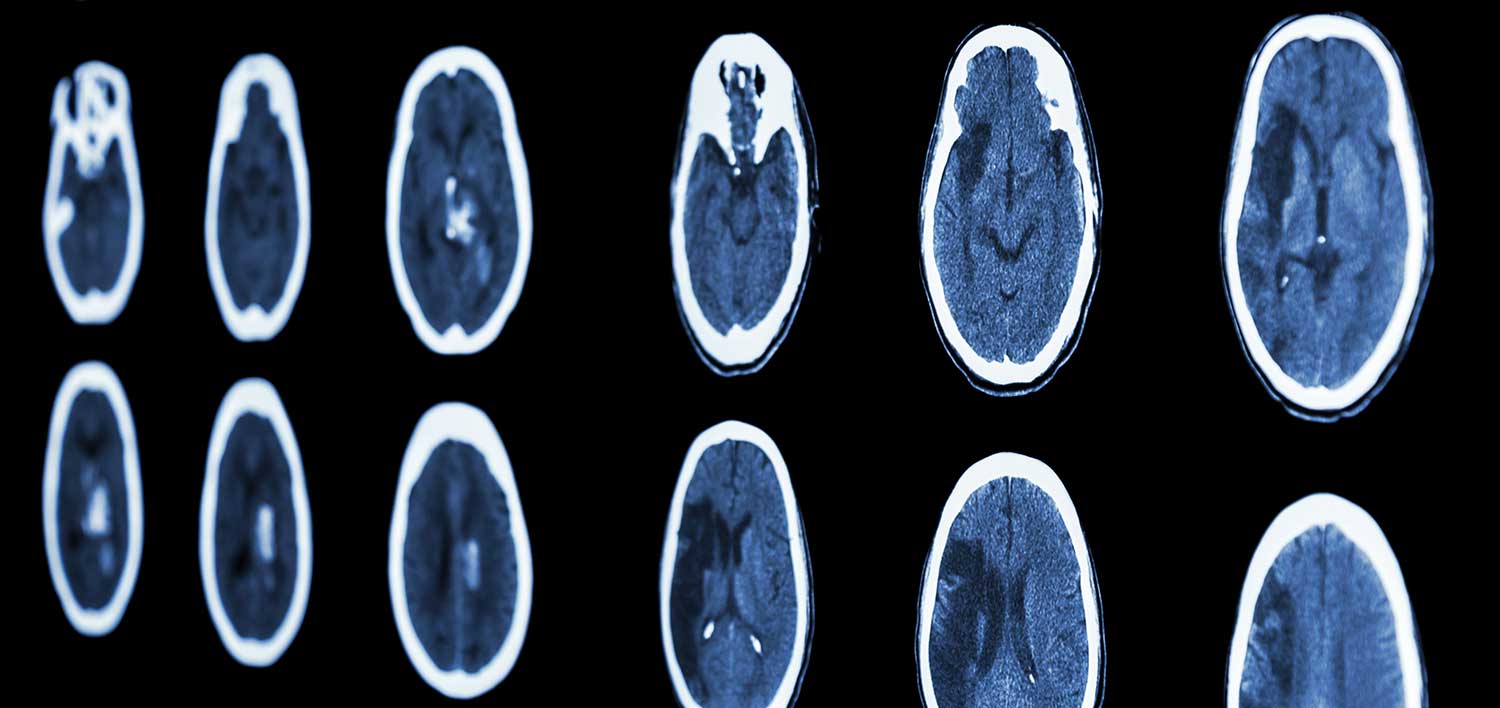

Can Blunt Force Trauma To The Head Cause Bleeding . The signs and symptoms of traumatic brain injury that have resulted from head trauma may be present right away or may take time to develop. This can depend on the severity of the injury, what sections of the frontal lobe. Head injuries can range in severity from a mild bump on. Brain aneurysms due to blunt and. For example, hitting one’s head against the steering wheel in a motor vehicle crash could cause blunt force trauma to the head. Frontal lobe damage from head trauma manifests in many different ways. Bleeding happens as the result of trauma to a blood vessel. Don’t ignore symptoms like severe headaches,. A head injury that causes bleeding within the skull may. This kind of trauma happens when a. There are two main types of trauma, and either may cause internal bleeding: The most common cause of an intracranial hematoma is a head injury. A head injury is any trauma to your scalp, skull, or brain.

Can Blunt Force Trauma To The Head Cause Bleeding There are two main types of trauma, and either may cause internal bleeding: For example, hitting one’s head against the steering wheel in a motor vehicle crash could cause blunt force trauma to the head. Don’t ignore symptoms like severe headaches,. Head injuries can range in severity from a mild bump on. This kind of trauma happens when a. Frontal lobe damage from head trauma manifests in many different ways. A head injury that causes bleeding within the skull may. Bleeding happens as the result of trauma to a blood vessel. The signs and symptoms of traumatic brain injury that have resulted from head trauma may be present right away or may take time to develop. There are two main types of trauma, and either may cause internal bleeding: Brain aneurysms due to blunt and. A head injury is any trauma to your scalp, skull, or brain. This can depend on the severity of the injury, what sections of the frontal lobe. The most common cause of an intracranial hematoma is a head injury.